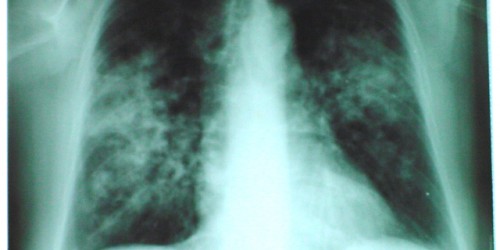

Granuloma in the lungs represents a small area of inflammation caused by a damage of the particular tissue. Granulomas in the lungs are not considered malignant growths. They typically affect small portions of lungs and apart from lung they may occur in any other part of the body. In majority of cases granulomas in the lungs develop as a consequence of inflammation and infection. These structural changes can be easily visualized on chest x-ray and may be sometimes mistaken for cancers.

A granuloma is a lump which contains a rough spherical mass of immune cells. In case of the presence of foreign cells the body normally sends certain cells in order to eliminate the foreign cells. However, if this attempt fails and foreign cells are simply not eliminated inflammatory cells surround the foreign cells and this is an initial phase of forming of a granuloma. Foreign cells include a variety of bacteria, fungi, keratinous substances, suture fragments etc. Apart from macrophages which are the most abundant components, granulomas also contain lymphocytes, neutrophils, eosinophils, multinucleated giant cells, fibroblasts and collagen.